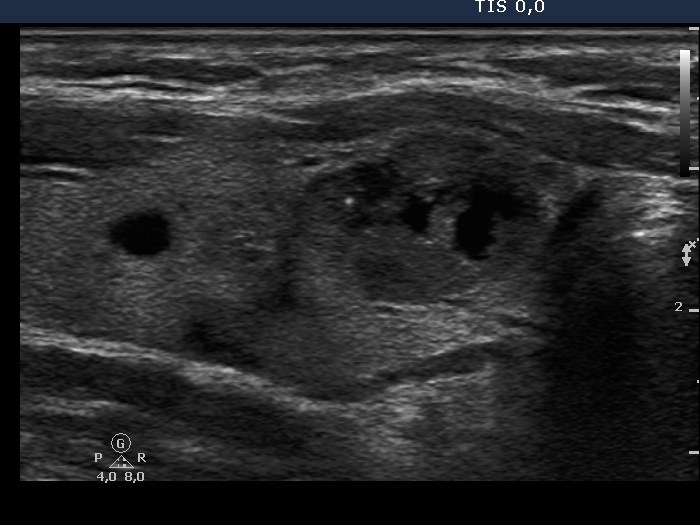

Follicular adenoma (histological diagnosis) - case cons 024 |

Benign hyperplastic nodules (histological diagnosis) - case 1091 |

Beside the very tiny granules and lines we find larger hyperechogenic granules, while the presence of similarly bright lines is spared. It is therefore ambiguous whether these figures are punctate echogenic foci or presentation of a connective tissue.

Several bright granules have dorsal pale tail therefore these and probably also the other granules lacking a tail belong to a comet-tail artifact subgroup.